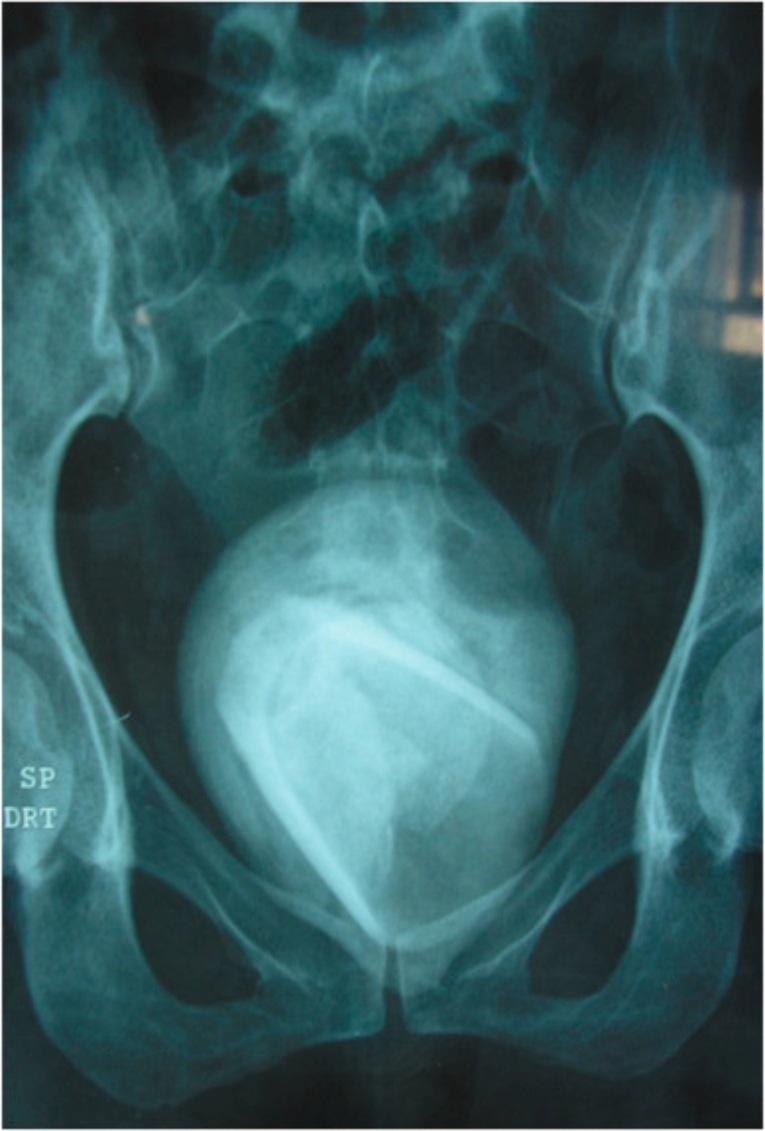

45-godišnja žena iz Tunisa došla je u bolnicu žaleći se na tipične simptome infekcije mokraćnog sistema. Međutim, nakon pregleda liječnici su ostali u šoku zbog otkrića. Naime, u njenom mjehuru pronašli su čašu obloženu bubrežnim kamencem širine 8 centimetara.

Žena je naposljetku otkrila da je čašu koristila kao seksualnu igračku prije nekoliko godina. Njen slučaj objavljen je u medicinskom časopisu Science, uključujući nevjerovatne snimke CT-a i sliku čaše i kamenca.